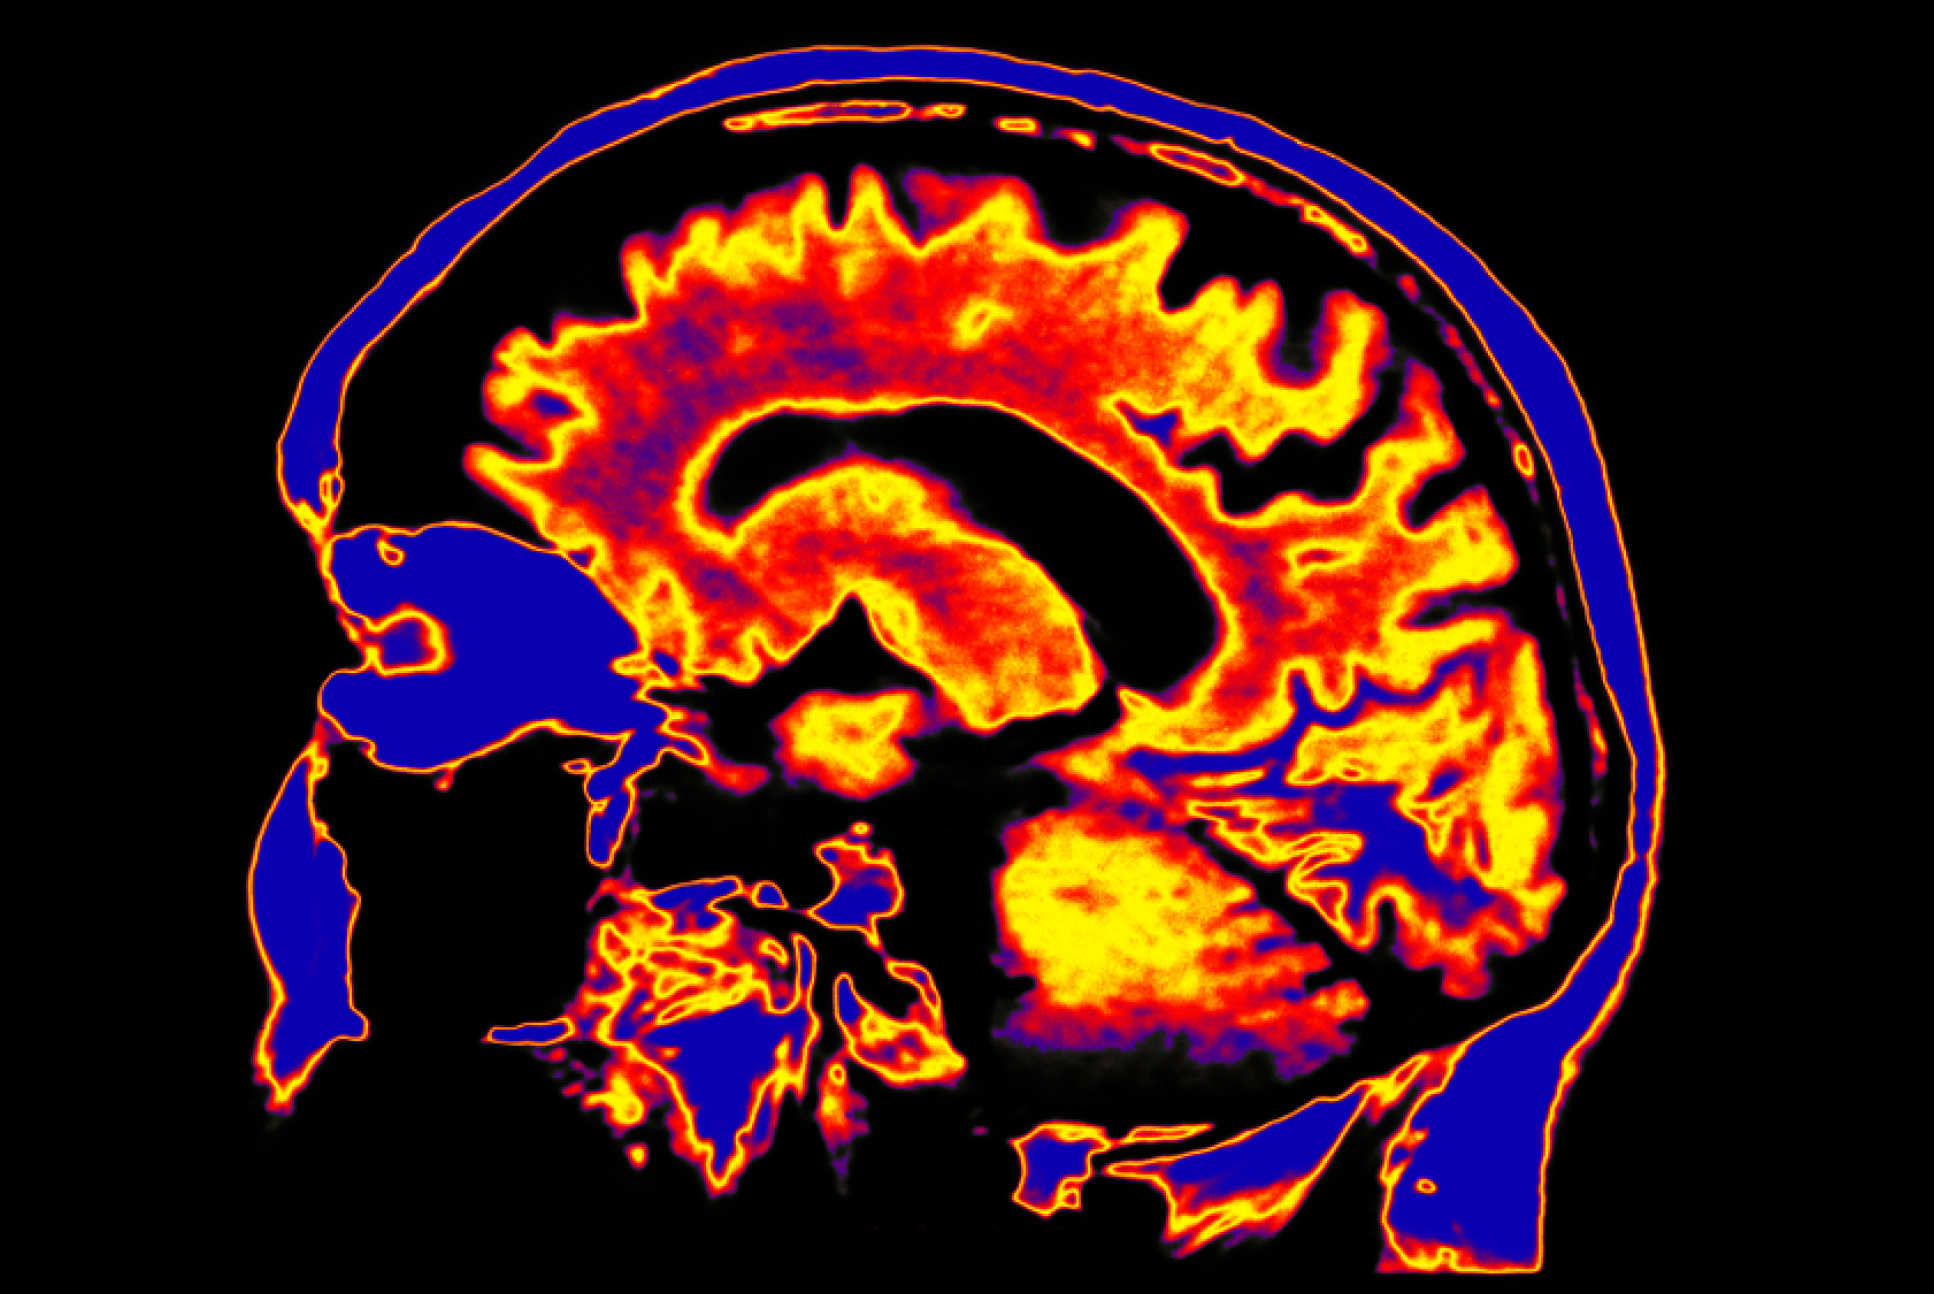

1. Imperial launches world’s first Centre for Psychedelics Research

Finally, the story reaching the top of the ‘most read’-chart in 2019 was the exciting launch of the first Centre for Psychedelics Research in the world. The Centre, which will be based at the Hammersmith Campus, will allow Imperial’s Psychedelic Research Group to continue their pioneering investigations into the effects of LSD, the study of psilocybin and potential use of psychedelics to treat depression. One aim is to develop a research clinic focussing on the use of psychedelic in mental health care and as tools to explore basis consciousness of the brain.